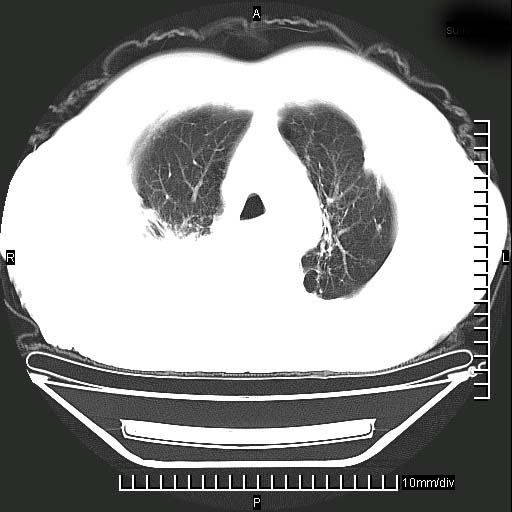

标题: CT24043:胸部增强:男性,60岁

既往肺结核,近10几天,咳嗽,咳痰,右侧胸痛,疼痛较明显,右上肺斑块考虑结核灶胸膜粘连,增强,可惜动脉期没有定好,未见强化,可延迟4分后又见较明显强化,中心见低密度影,如果说结核是边缘强化,可这个灶强化的面积挺大的,让人很挠头。

延迟4分后

强化的组织可能是膨胀不全的肺组织或炎性肉芽组织。

1)两肺继发性肺结核。2)右侧胸膜增厚+少量胸腔积液。